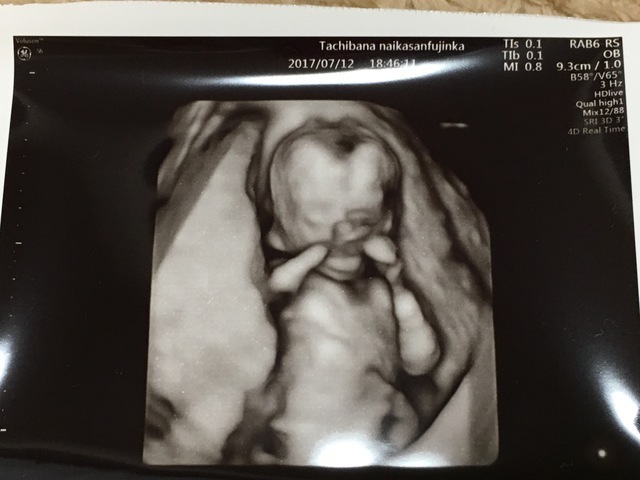

16週4日(16w4d・男の子)|みさき さん(27歳)

エコー写真撮影時のエピソード:

つわりが長く16週でやっと落ち着いてきた頃でした。辛いつわりのなか、4Dエコーで赤ちゃんを見れるのだけが楽しみでした。エコーで性別がわかったのもこの頃。

手を後ろに組んで、足を広げてたのでお腹の中でくつろいでいたようでした。

生まれてきてもこの格好を良くしています。